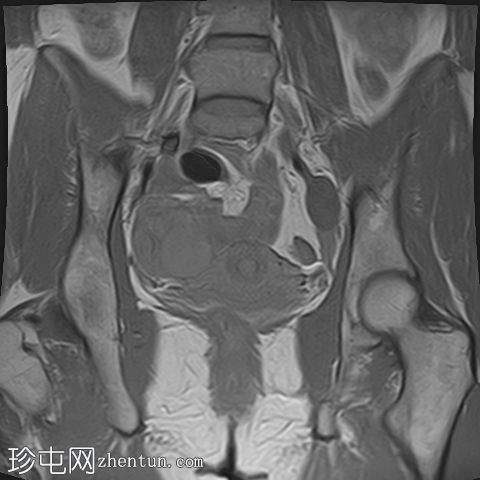

冠状位

T1

右侧卵巢出血性囊肿,T1成像呈中等信号,T2成像呈高信号,伴有薄内部分隔

左侧卵巢出血性囊肿,信号特征与右侧囊肿相似

左侧单纯性卵巢旁囊肿,T1成像呈低信号,T2成像呈高信号

此外,所有囊肿均未显示弥散受限或实性成分强化。

所有囊肿均仅显示薄层外周壁强化。

道格拉斯囊右侧可见轻度积液。

还存在偶发的塔洛夫囊肿。

卵巢相关囊性病变边界相对清晰。信号特征可能因出血时间而异。

T1 加权成像:大多数病变呈低信号,也可能包含中至高信号成分。

T1 脂肪饱和度:通常显示中至高信号。

T2 加权成像通常显示高信号。 T2 阴影征提示存在慢性血液产物,更像子宫内膜异位症。

T1 增强钆:未见强化。

本例卵巢囊肿呈中等 T1 信号,类似于肌肉信号,T2 信号高,伴有薄内隔和外周壁强化。但无内部强化或弥散受限。STIR 序列显示与 T2 一致的信号,无任何脂肪成分。该表现提示卵巢出血性囊肿处于早期或消退期。

此外,左侧卵巢旁囊肿外观简单,T1 信号低,T2 信号高。